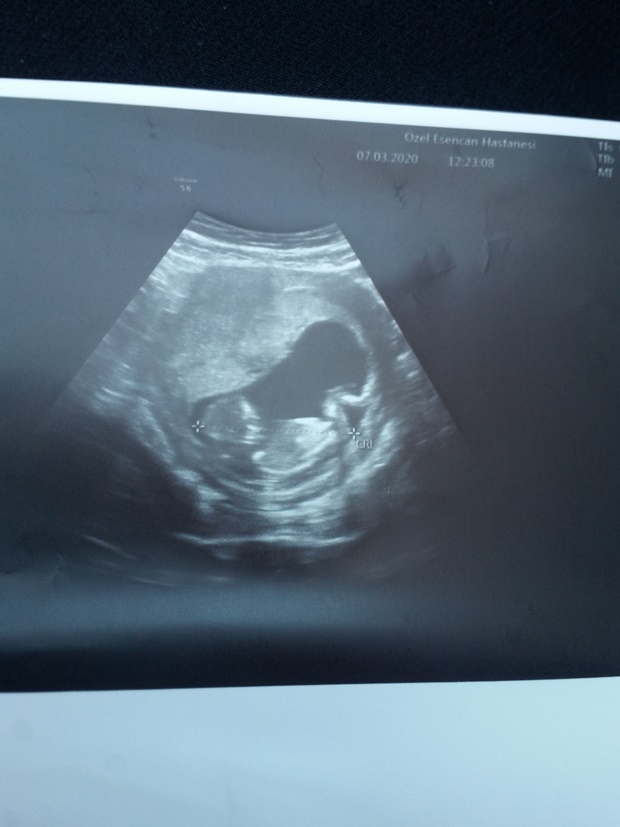

Nub teorisiyle cinsiyet tahmini bebeğim erkek mi kız mı ?

Banada yorum.yapin lutfen 12 haftaligiz

Nub teorsisi için cinsiyet tahmininde yorum isteyen arkadaşlar lütfen uyarımızı dikkate alın. Ultrason görüntüleri elinize ilk verildiği gibi net olmaz. Sık sık ışığa maruz kaldığı için görüntü kalitesi bozuluyor dolaysıyla bizlerde değerlendirme yapamıyoruz. Sizlere yorum yapabilmemiz için görüntü kalitesi aşağıdaki linkte yer alan görseller gibi olmalıdır. Ayrıca Bebeğin cinsiyeti net olarak 18-19-20. haftalarda belli olur..

Merhaba, yüklediğiniz görsellerde nub çıkıntısı anlaşılmıyor , dolaysıyla değerlendirme yapamıyoruz.. Görselin kalitesi aşağıdaki gibi olmaldır.. Sağlıklı gebelik süreci diliyorum.